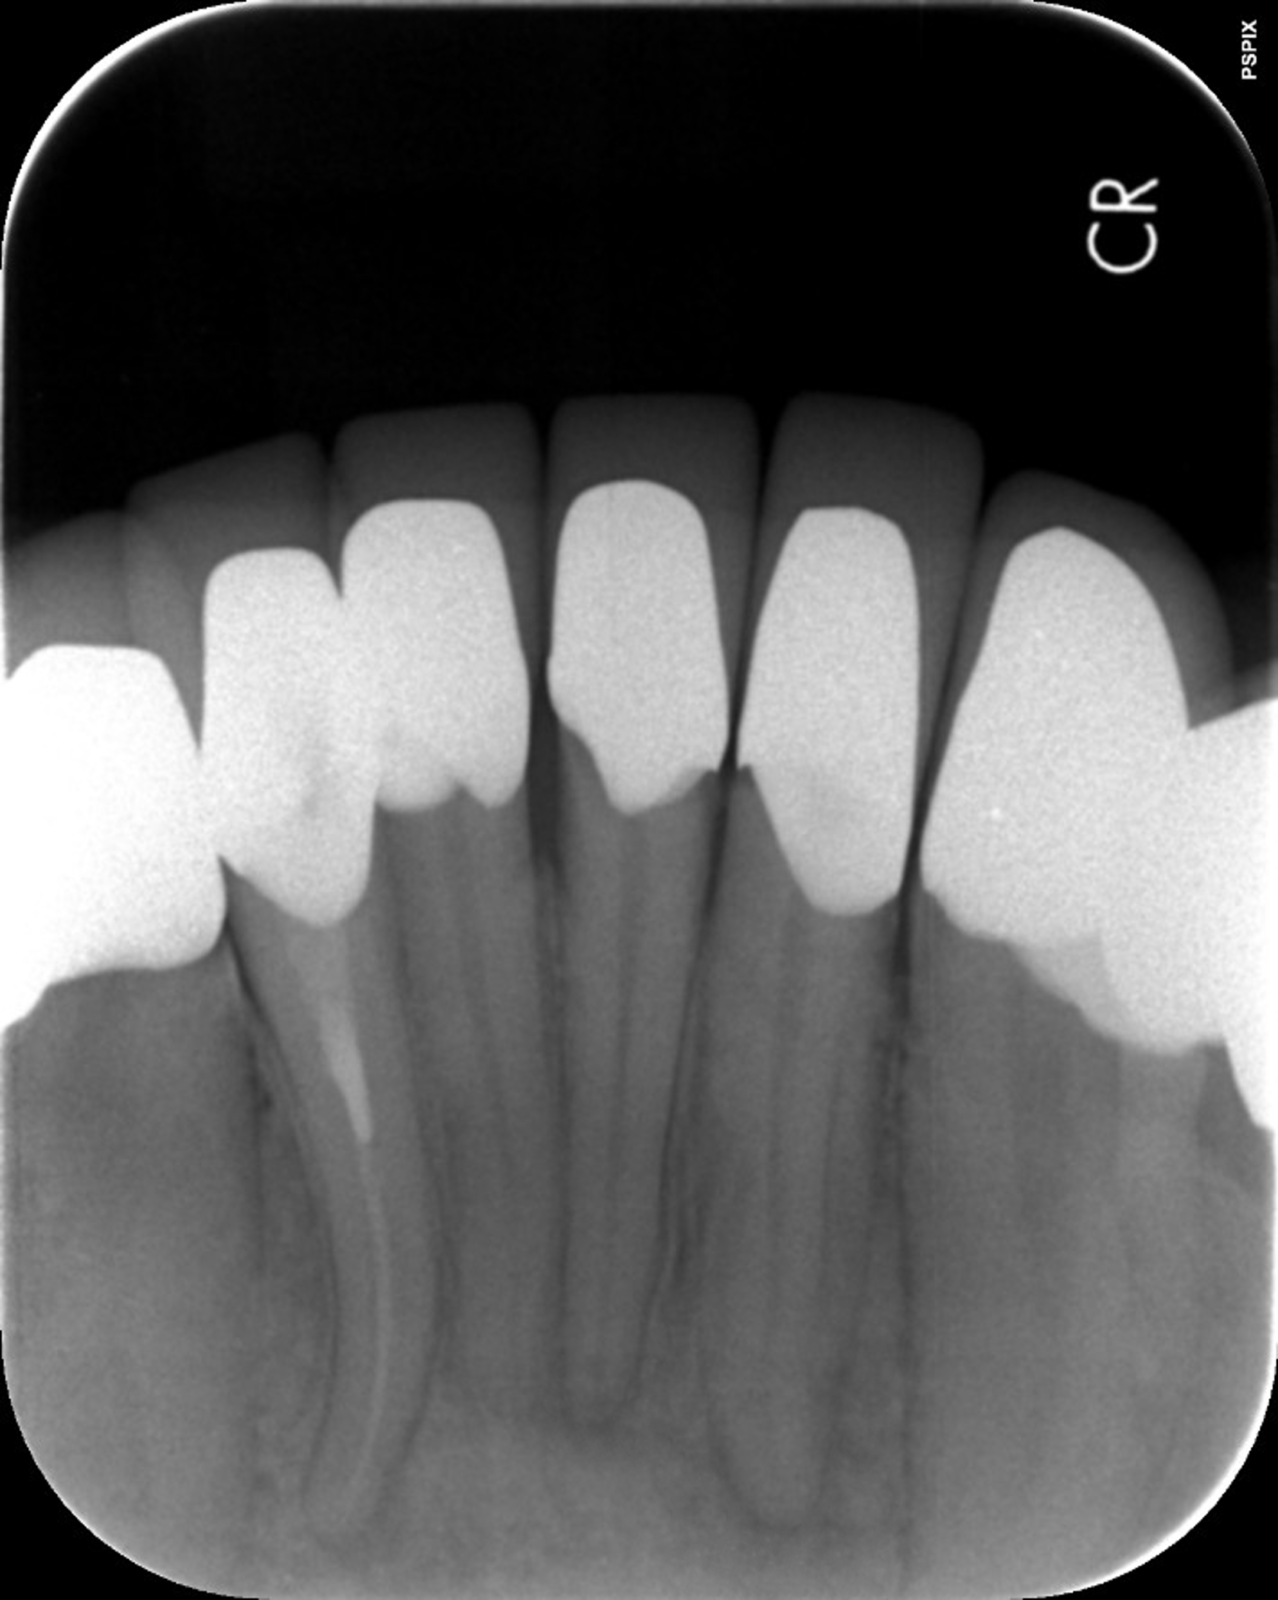

次の画像は、同じ患部をCTとレントゲンで撮影した画像です。

• 比較

「左」の写真がCTで、「右」の画像がレントゲンで撮影したものです。

赤丸で囲んだところには、黒い影が見えます。ここには炎症が起こっているのですが、右の写真には影がありません。つまり、2次元のレントゲンだけで診断した場合、問題のある部分は治療しない選択をするため、最終的には抜歯の運命をたどるケースです。